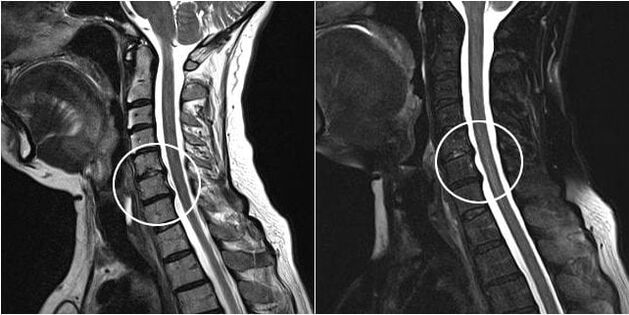

Osteochondrosis of the thoracic spine of the 3rd degree is accompanied by destruction and rupture of the fibrous tissues of the disc, release of the central part, that is, the formation of a hernial protrusion of the intervertebral disc occurs. As a result, nerve roots begin to be compressed, nearby vessels are compressed, and veins and arteries are compressed.

The last and most severe stage of the disease is characterized by displacement, torsion, deformation of the vertebral bodies, a further increase in their area and proliferation. The affected fibrous tissue of the disc begins to be replaced by bone tissue in the form of specific growths - osteophytes, compressing the spinal cord. As a result, spinal mobility is significantly reduced.

If symptoms of thoracic osteochondrosis appear, it is recommended to consult a neurologist, who, after examining the back and examining the spine in different positions of the patient, will be able to make a primary diagnosis. To determine the extent of the damage, X-rays, MRI or CT scans are prescribed. Treatment tactics depend on the results obtained.

Surgical treatment is necessary if there is compression of the spinal cord by a fragment of the intervertebral disc. In this case, laminotomy can be performed - excision of the vertebral arches, or discectomy - removal of part of the intervertebral disc or its complete removal with the installation of a graft. In clinics with modern equipment, surgical procedures are performed using low-traumatic methods through small incisions.